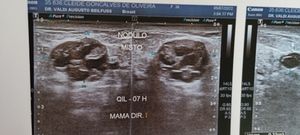

Me chamo Cleide tenho 36 anos e estou precisando de ajuda pois descobri que tenho três nódulos nos seios e um deles está com um tamanho preocupante por isso preciso passar por consulta com um mastologista só que na cidade aonde eu moro não tem então vou ter que me locomover até outra cidade e meu esposo vai ter que ir junto por causa da nossa bebê que ainda mama no peito e não temos condições de pagar nossas passagens e os custos com comida peço encarecidamente a ajuda de vcs muito obrigado.

Nódulo